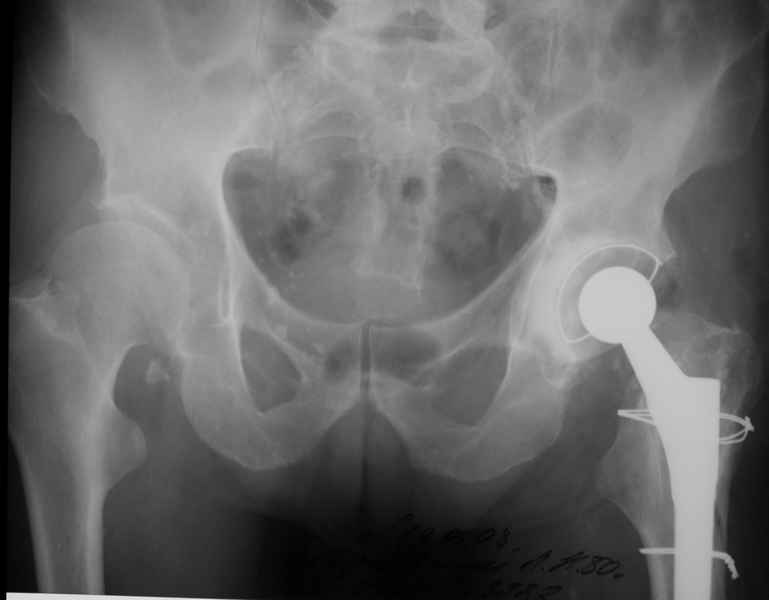

2. Применение ножки дистальной фиксации, мы отдаем предпочтение ножке Вагнера с фиксацией проксимального отдела на ножке. Более травматичное вмешательство, но при стабильной фиксации ножки реабилитация идет в обычном режиме.

Хочется показать два подобных случая, П-ка Зубарева 72 лет и п-т Гладковский 80 лет. Сразу принимаю замечание, что это были ножки цементной фиксации, просто под руками не было бесцементника.